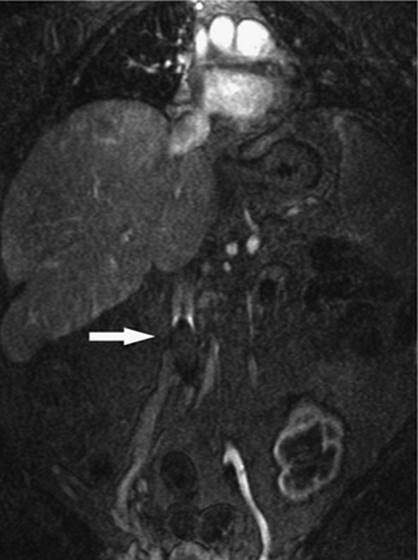

000450

Figure 35.20. Patient with cirrhosis undergoing a transjugular intrahepatic, portacaval shunting (TIPS) procedure. Catheter (white arrow) is positioned from a hepatic venous approach, through the hepatic parenchyma into the portal vein (black arrow). (Image courtesy of Harry K. Meisenbach, MD.)

Transjugular intrahepatic portacaval shunting (TIPS) was first conceived of and performed in dogs in 1969 by Josef Rosch et al. (36). The first human case of percutaneous TIPS was reported in 1988 (37). It is an effective nonsurgical and nonendoscopic means to control variceal bleeding by decompressing the portal venous system (38). A CT scan, ultrasound, or MRI is recommended to evaluate for patency of the portal vein as well as exclude hepatic neoplasm and evaluate for other anatomic considerations. The usual laboratory studies to check for hematocrit and coagulopathy should also be performed. IV antibiotics should be administered prior to the procedure. The technique consists of a percutaneous approach, usually ultrasound-guided canalization of the right internal jugular vein. From this approach, access is gained to the hepatic veins and pressure measurements are made from the portal vein using a wedged technique to the right atrium. A hepatic venogram is performed, followed by angiogram of the portal vein, using carbon dioxide and either a wedged technique or puncture of the hepatic parenchyma through the jugular access. Passage of a long curved needle is then performed from a satisfactory location in the hepatic vein, usually the right hepatic vein, into the identified location in the intrahepatic portion of the portal vein or its branches. Direct pressure measurements are made using the transjugular pathway (Fig. 35.20). If acceptable, balloon angioplasty of the intrahepatic tract between the hepatic vein and the portal vein is then performed. A stent, usually covered, is deployed from the portal vein to the hepatic vein through the tract to keep it patent and prevent hepatic recoil and restenosis (Fig. 35.21). Repeat pressure measurements are performed to confirm satisfactory pressures have been reached. Any additional adjustments that need to be made to the stent can be performed at this time, as well as embolization of varices if indicated.